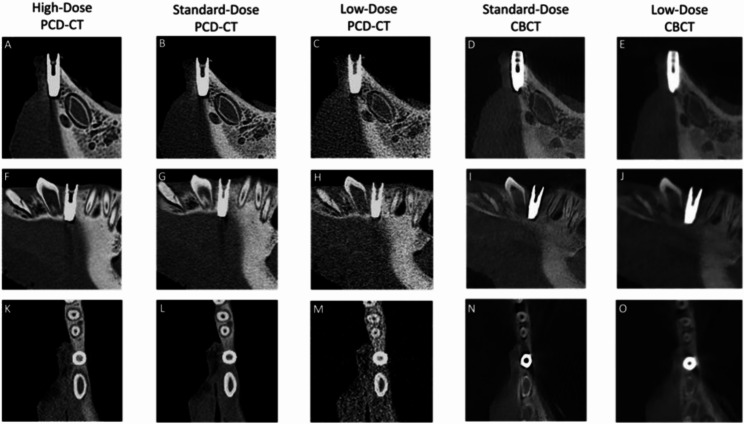

Methods: This ex vivo comparative study of porcine specimens assessed five imaging protocols with both CBCT and PCD-CT at three effective radiation dose levels (high: 360µSv, standard: 145µSv, low: 20µSv) to evaluate image quality, artifact burden, metal artifact susceptibility, and quantitative bone measurements in the mandibular region. Three blinded readers analyzed the data using a 5-point Likert scale (5 = highest to 1 = lowest rating) and performed linear bone measurements at implant planning sites. Statistical analysis included descriptive statistics and inter-reader reliability assessment using intraclass correlation coefficients (ICC).

Results: Each reader evaluated 30 data sets (12 CBCT, 18 PCD-CT), with 24 implant planning sites per imaging protocol. High-dose PCD-CT demonstrated the best image quality and diagnostic interpretability (4.89 ± 0.27), followed by standard-dose PCD-CT and CBCT (4.50 ± 0.73; 4.33 ± 0.61), with low-dose protocols showing intermediate quality with higher artifact burden. In comparison to CBCT, PCD-CT demonstrated superior performance in reducing implant-induced artifacts across all protocols. Quantitative bone measurements showed minimal variability, meeting clinical precision requirements for computer-assisted implant surgery. Both qualitative (ICCs:0.70-0.89; p < 0.001) and quantitative (ICCs:0.79-1; p < 0.001) analyses demonstrated high reliability, regardless of the reader's experience.

Conclusions: PCD-CT demonstrated superior image quality and reduced artifacts compared with CBCT at all radiation dose levels. These findings highlight PCD-CT's potential to enhance implant planning and improve clinical outcomes with reduced radiation exposure while maintaining diagnostic accuracy.